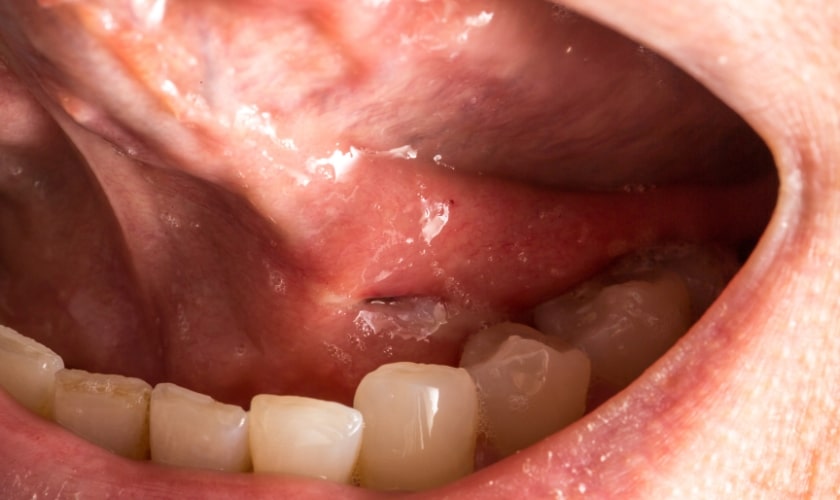

- White or Red Patches Inside the Mouth: Leukoplakia (white patches) and erythroplakia (red patches) on the tongue or inner cheeks, especially if they persist, can be precancerous lesions or signs of early oral cancer.